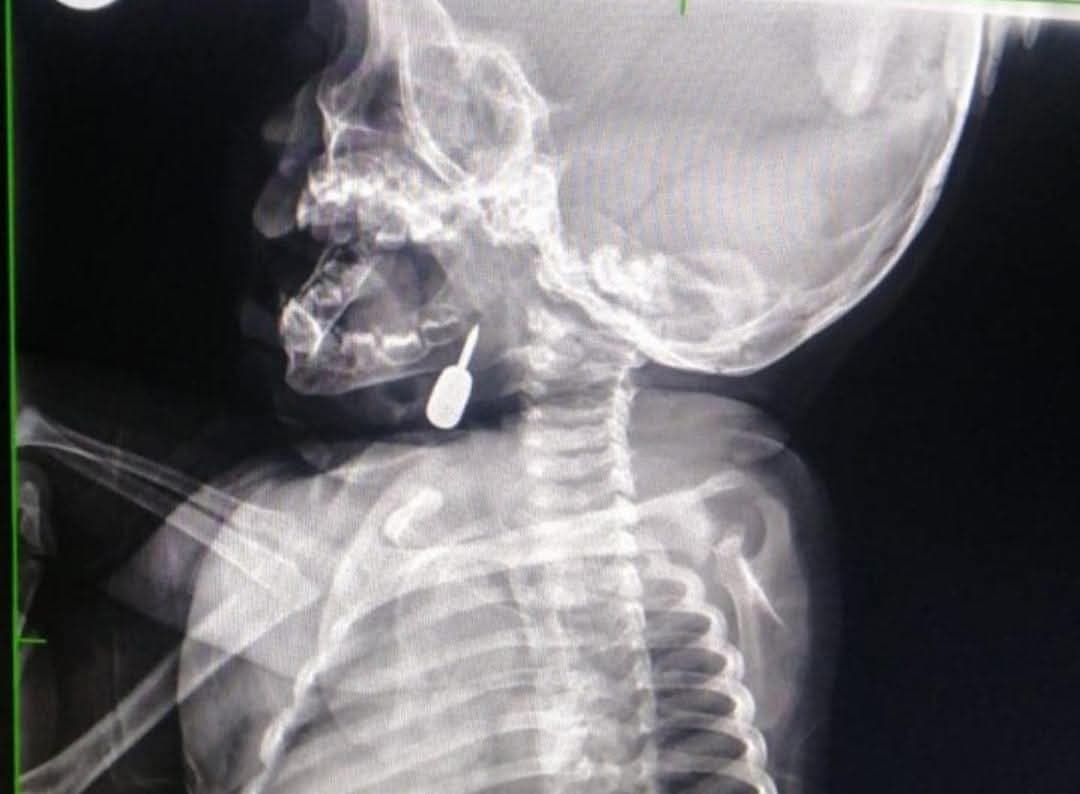

إجراء طبي نوعي ينقذ حياة طفل من موت محقق في عمّان